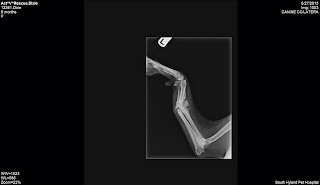

| x-ray before |

This

is a nasty break. She's lyme positive and scabies too.Dixie's leg surgery was 1 1/2 hours long by a board certified surgeon. He got her leg

straightened our almost 100%!

She should do really well. I would estimate her now at 1 1/2 yrs old. Dr. Murphy did an amazing job and I followed up doing the spay.